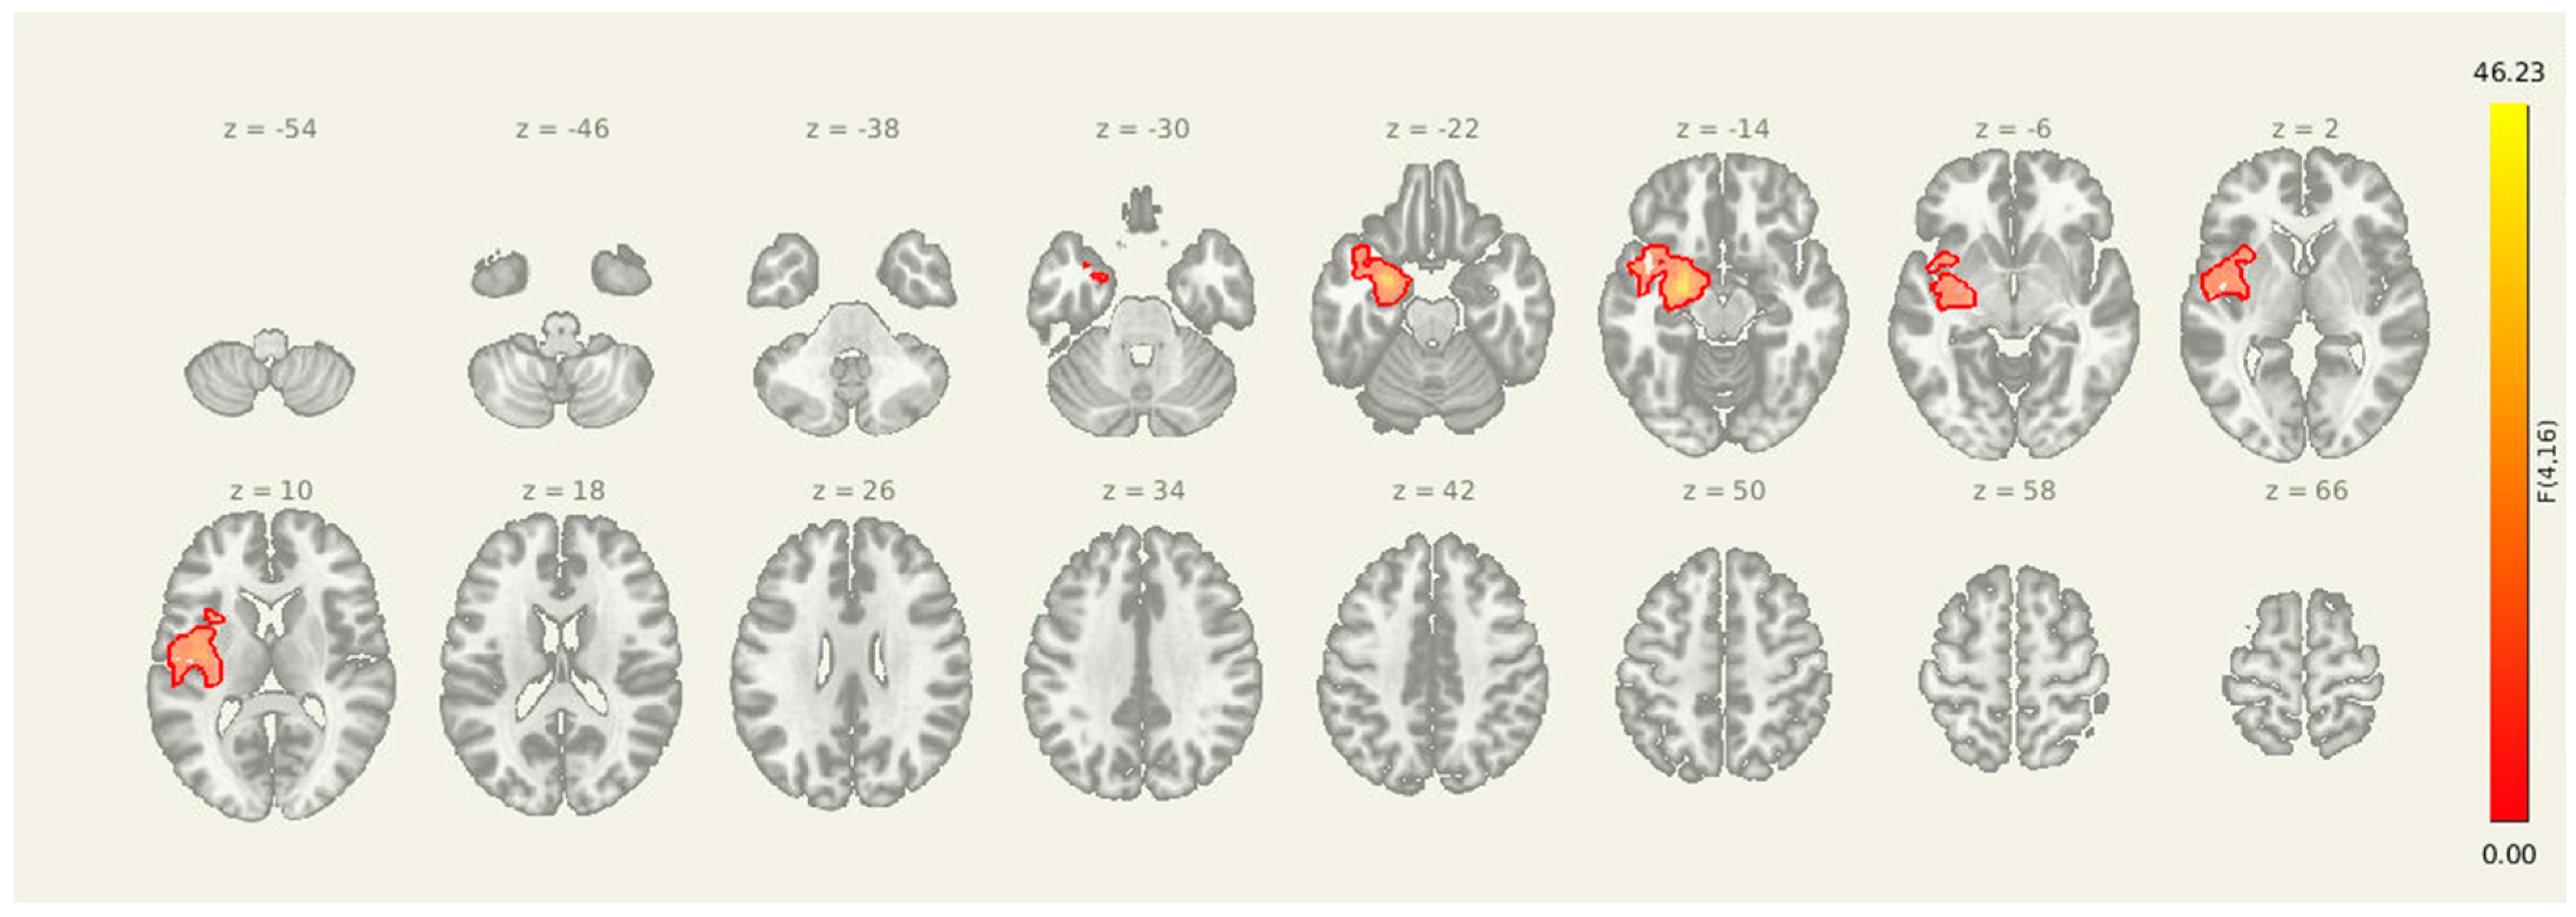

3.5. Amygdala-Insula-Thalamus Seed

Seeding from amygdala-insula-thalamus (Figure 4 and Table 6) revealed a significant post-intervention reduction in connectivity from the insula, amygdala, and thalamus to a cluster in the right superior frontal cortex (MNI coordinates: +20, +18, +56; cluster size = 133 voxels; p-FDR = 0.0065). These results suggest that improved prefrontal oversight may be a key mechanism through which the intervention alters pain-related brain dynamics in individuals with post-stroke headache.

Figure 4.

Post-intervention reductions in connectivity from limbic seed regions. Significant decreases in seed-to-voxel connectivity were observed from the amygdala, insula, and thalamus following the intervention. Clusters included sensorimotor, frontal, and subcortical regions. Results are thresholded at p-FDR < 0.05.